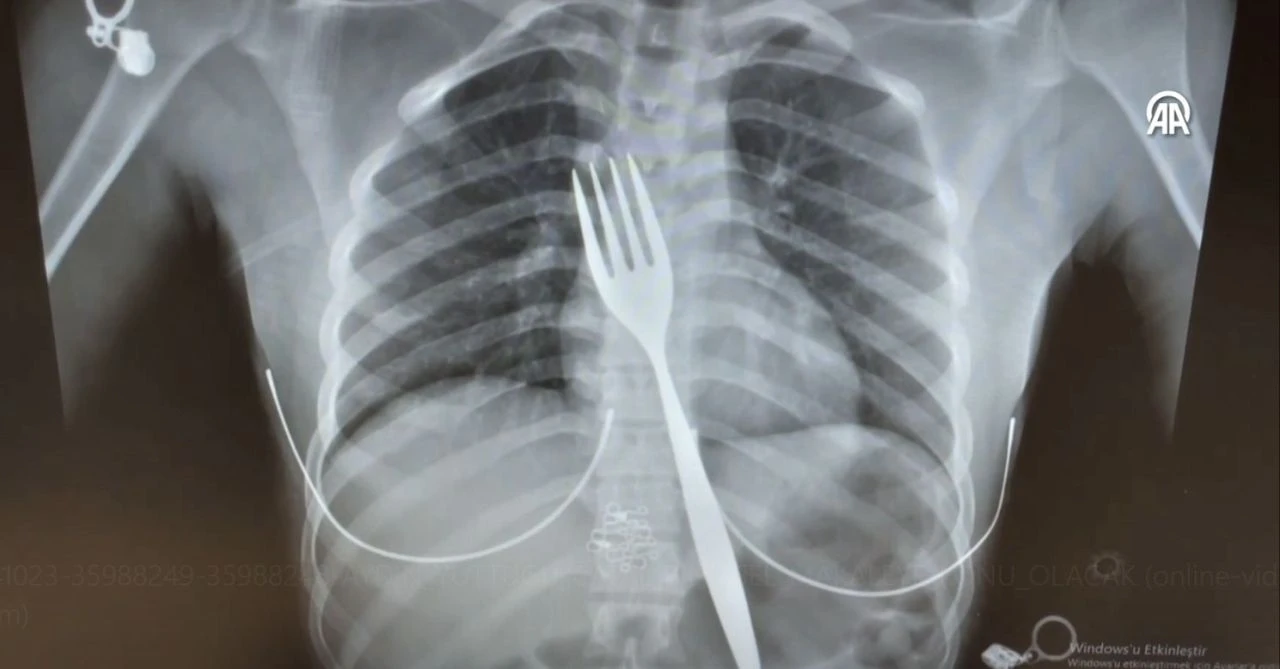

Aydın'da yabancı uyruklu 18 yaşındaki E.E., doktorları bile şaşkına çevirdi. çatal yutan genç kız ambulansla hastaneye kaldırıldı. Yapılan tetkikler sonucu genç kızın yemek borusunda çatal tespit edildi. Doktorları bile şoke eden olayda çatal önce endoskopi ile çıkarılmaya çalışıldı ancak tehlike fark edilince E.E. ameliyata alındı.

Dr. Akay Edizsoy, "Büyük bir çatalın tamamen yutulması şeklinde ortaya çıkan bu vakayı ilk duyduğumda doğru olmadığını düşündüm. Hasta 18 yaşında ve yabancı uyrukluydu. Türkçesi biraz zayıf olduğu için belki de yanlış anlaşılmalar olabileceğini düşündük. Ama hastanın filmini çektiğimizde gerçekten bir çatalın yemek borusunda olduğunu gördük" diye konuştu.